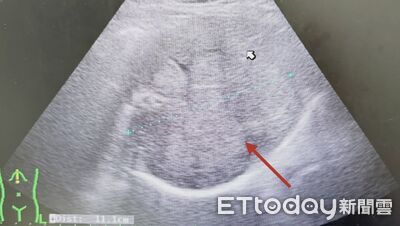

有不少人以為腫瘤只要手術切除就畢業了,但若忽略術後追蹤,恐後果慘烈。胃腸肝膽科醫師張靖分享,近日收治一名上腹不適的患者,一照超音波赫然發現「無數的腫瘤」正密密麻麻地佔據整個肝臟。追問病史才發現,他雖然7~8年前曾開刀切除腫瘤,但術後自覺無礙就沒再回診,如今慘況連醫師都忍不住搖頭。 《詳全文...》